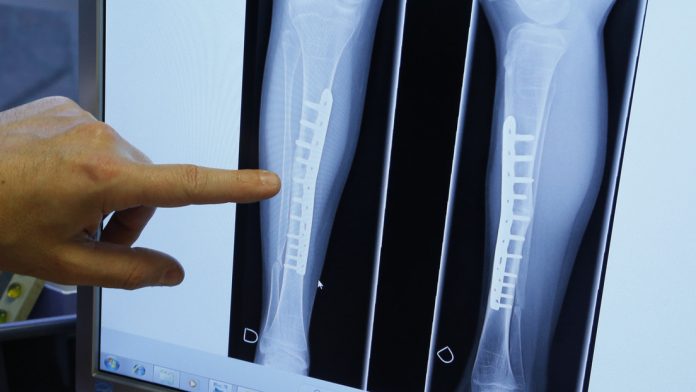

Los veganos tienen mayores probabilidades de sufrir fracturas de huesos que los consumidores de carne, según se desprende de un estudio británico recientemente publicado en la revista BMC Medicine. El trabajo concluyó que aquellos que renuncian a los productos de origen animal tienen un 43 % más de riesgo de padecer fracturas óseas en cualquier parte del cuerpo, incluidas roturas completas.

En total, la investigación, realizada por científicos de las universidades de Oxford y Bristol, incluyó alrededor de 55.000 participantes de todo Reino Unido que estuvieron bajo observación por casi 18 años para detectar la presencia de cualquier tipo de roturas. Para mediados de 2016, se observaron 3.941 casos de fracturas totales y la mayor diferencia entre los veganos y los consumidores carne se presentó en las probabilidades de sufrir una rotura de cadera, que en el caso de los primeros era 2,3 veces más alta.